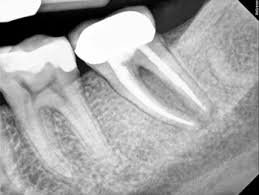

Each tooth has a soft tissue – the pulp which nourishes the tooth. Because of deep decay, injury, or gum disease, the pulp tissue in your tooth has become inflamed or infected. In any other part of your body, if a similar tissue becomes diseased, the body merely throws it off and forms new tissue. However, a tooth is a unique and different. Because the infected soft tissue (pulp) within the tooth is totally encased within hard tissue, it is the role of the dentist to remove the soft tissue located in the root canals, cleanse the area, and finally fill the canals with a special material so that bacteria cannot re-enter the tooth to cause another infection. When the endodontic treatment is complete, the tooth is by no means "dead". It receives quite adequate support from the surrounding tissues and may be expected to last as long as any other natural tooth.

After the diseased pulp is removed, the pulp chamber and root canals are flushed and cleaned

Step 3 Filling the root canals